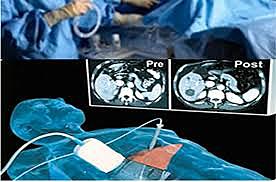

Raymond V. Damadian,con un trabajo hoy clásico y que, como se refleja en los trabajos posteriores de Mallard y de Hollis, fue un aporte desafiante que estimuló el desarrollo pos-terior de la RM.

Aquí, Damadian propone: “Las medidas de resonancia spin-eco pueden ser usadas como un método para discriminar entre tumores malignos y tejido normal”. El encontró diferencias en T1 y T2 entre seis muestras de tejidos normales y dos tumores sólidos del hígado y el riñón de la rata. -

Además, comparó fibroadenomas con dichos tumores, encontrando que también se diferenciaban de ellos. Así, los valores de T1 y T2 de tumores se encontraban fuera del rango de los valores normales y de los fibroadenomas. Damadian apodó al método analítico para diferenciar los valores de relajación “FONAR” (field focused nuclear magnetic resonance). Sus resultados los corroboró con tejido humano en 1974

Siguió trabajando con su equipo construyendo el primer tomógrafo de RM de cuerpo entero que llamaron “el indomable” obteniendo la imagen de un tumor en una rata, publicada en la revista Science en 1976.